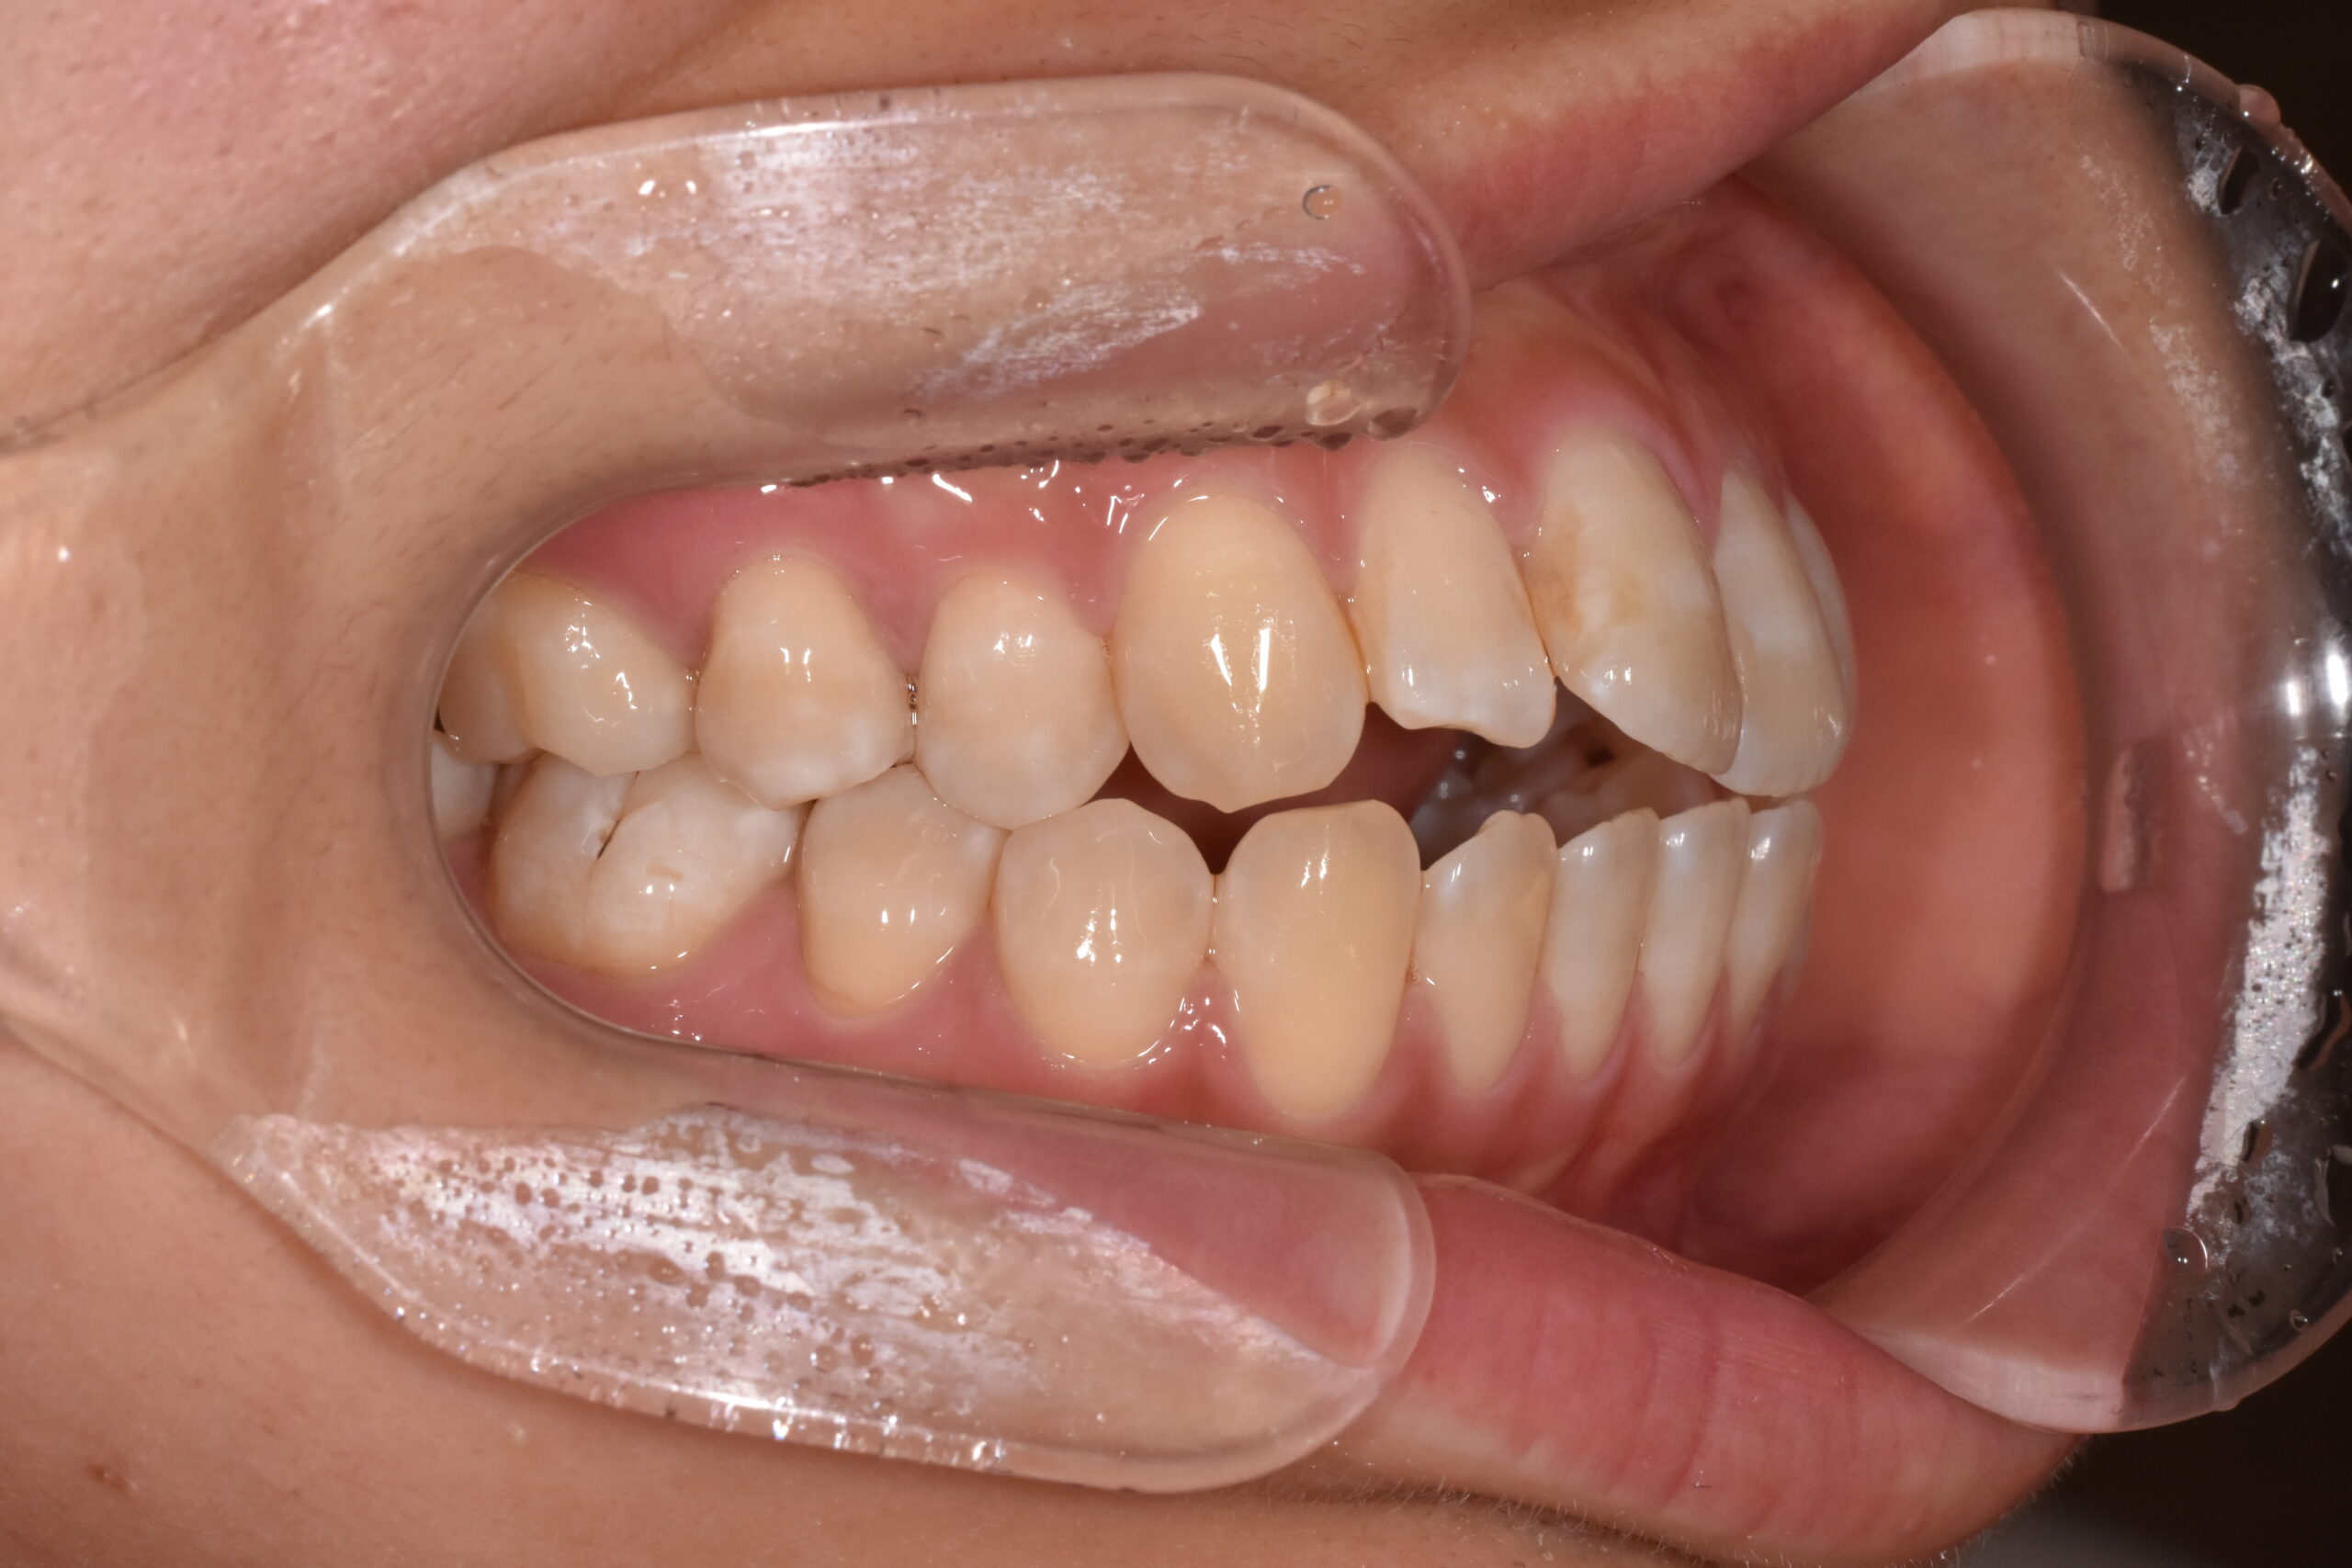

治療前

骨格:開咬傾向(前歯が噛みにくいタイプ)

歯並び:前歯が噛み合わない(開咬)+前歯の突出傾向